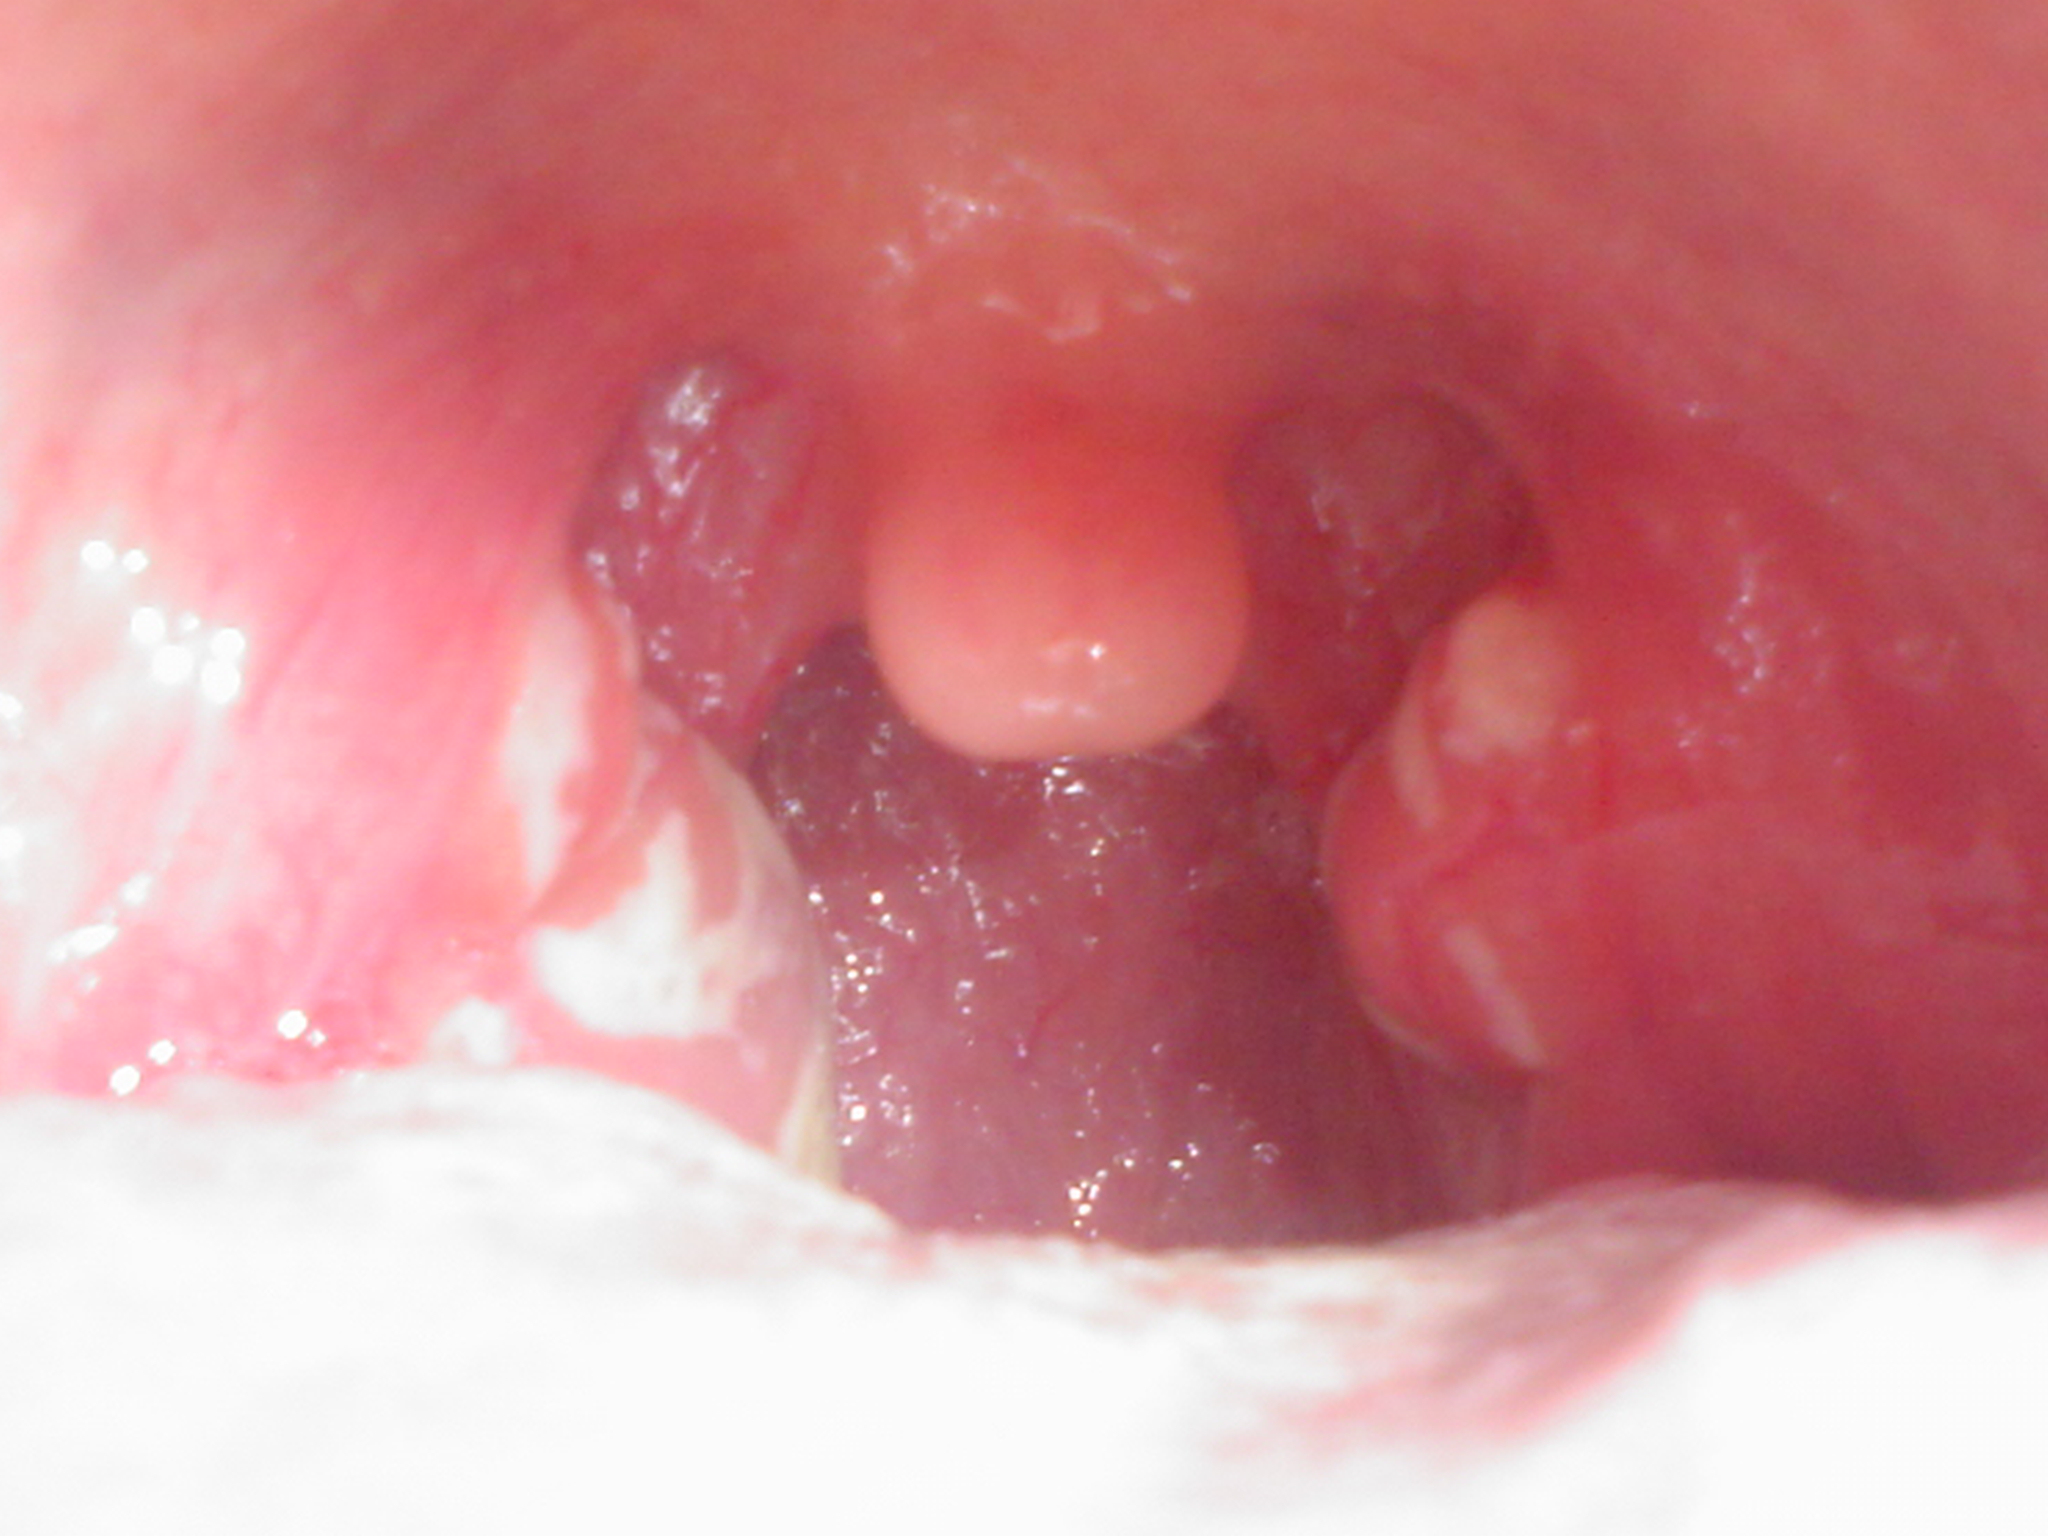

연쇄상구균 인두염은 A군 연쇄상구균( ''Streptococcus pyogenes'')에 의해 발생하는 상기도 감염으로, 다양한 합병증을 유발할 수 있다.[44] 재발성 감염은 합병증 발생 가능성을 높이며, 치료 부족[45]과 신체의 면역 반응이 추가적인 부작용의 원인이 된다.[46]